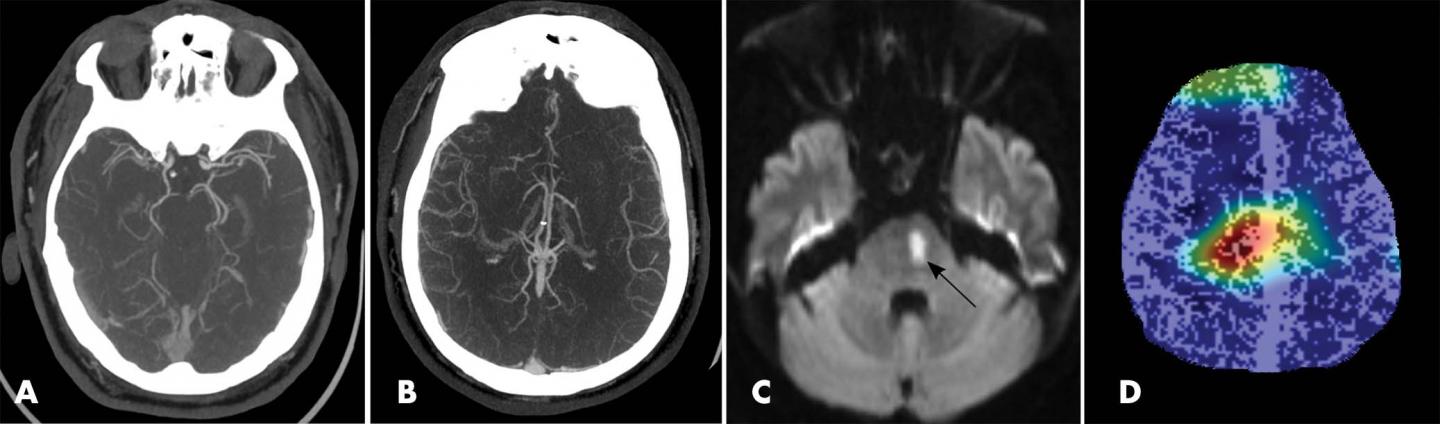

Working closely with Brown's computer science department, the researchers developed a deep learning model from scratch. They used a large sample of CTA examinations for patients with suspected acute ischemic stroke to train the algorithm to recognize the appearance of large vessel occlusions and distinguish it from other conditions. Preprocessing of the CTA exams included the creation of maximum intensity projection images to emphasize the contrast-enhanced vasculature. The researchers also used multiphase CTA, a newer approach that provides more comprehensive information than the single-phase technique.

When they tested the deep learning model on multiphase CTA examinations of 62 patients, the model detected all 31 large vessel occlusions for a sensitivity of 100%, a statistically significant improvement over the 77% sensitivity rate of single-phase CTA. The use of multiphase CTA contributed to the improved performance.

The study is the first to use multiphase CTA to look at occlusions in both the arteries of the front, or anterior, part of the head and neck and those in the back, or posterior.

"Posterior circulation occlusions have not been discussed much in machine learning literature," Dr. Stib said. "They're less common but have pretty profound clinical consequences if missed. It's important to have an algorithm that detects all categories of occlusion, both anterior and posterior."